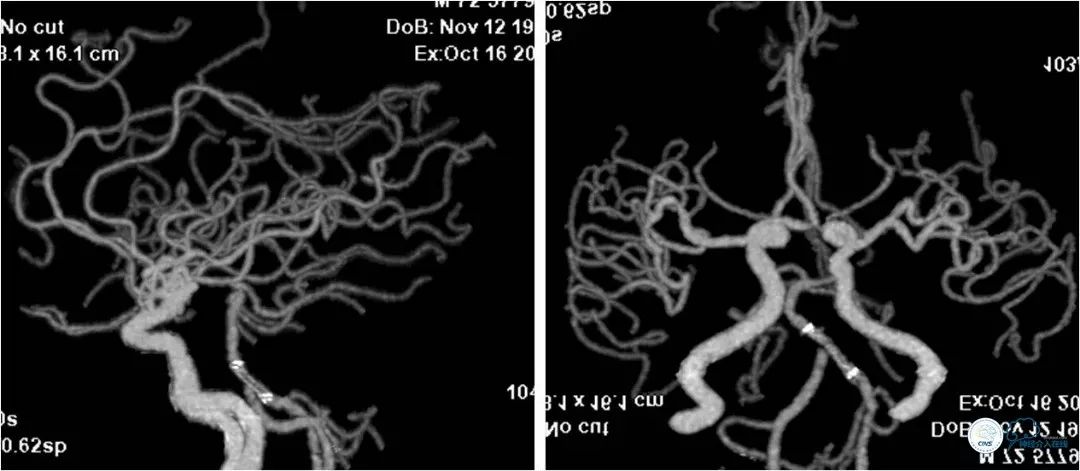

头部CTA:双椎动脉-基底动脉交界区重度狭窄(图3)。

术后复查头颅CTA:基底动脉支架内通畅(图12)。